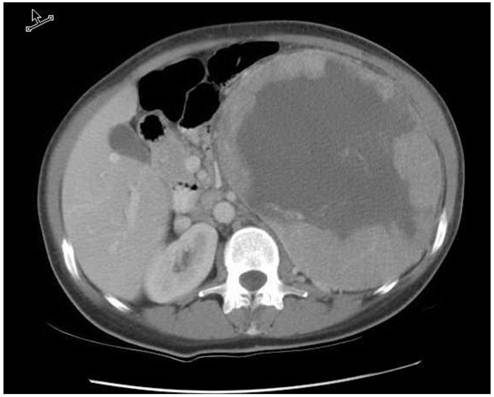

Review of our institutional database revealed a single patient with metastatic chromophobe RCC treated with targeted therapy. In February, 2000, a 45 year-old woman presented with fatigue, weight loss, and a large palpable abdominal mass. A CT scan of the abdomen demonstrated an 18 cm left renal mass (Figure 1). She underwent a left sided radical nephrectomy and final pathology demonstrated a T2, chromophobe renal cell carcinoma (RCC) with areas of sarcomatoid transformation. She was followed closely with periodic surveillance and was free of disease for 6 years. In June 2006, she presented with multiple small liver nodules; laparoscopic resection of a hepatic lesion confirmed the presence of metastatic chromophobe RCC. Once recovered, she was placed on sunitinib (50mg orally on a four-weeks on, two-weeks off schedule) and had regression in some of the liver lesions.

Figure 1

CT scan with IV contrast demonstrating the 18 cm left renal tumor prior to radical nephrectomy in 2002.